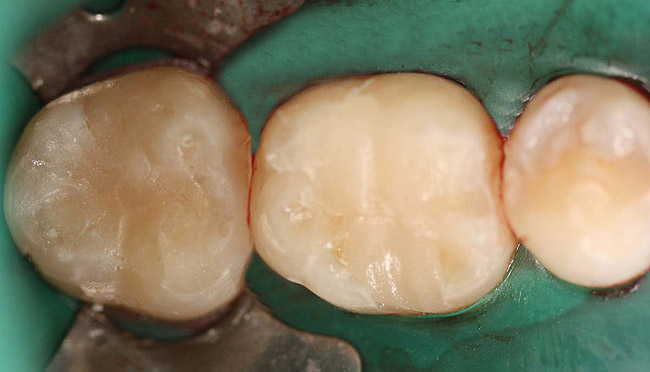

Case 1 (Figure 1 through Figure 6) reveals a mandibular first molar with severe wear and a defective amalgam. The amalgam and decay were removed, the tooth was prepared, and bonding to enamel and dentin was completed. An initial layer of composite was placed and cured, followed by many subsequent layers to minimize the negative effects of shrinkage. The composite was shaped and initial polishing was completed. Occlusion was adjusted, final shaping was accomplished and polishing was completed.

Figure 4. Restoration after placement of the final layer.

Figure 4

Figure 5 Final restoration after removal of the oxygen-inhibited layer, shaping, and polishing.

Figure 5